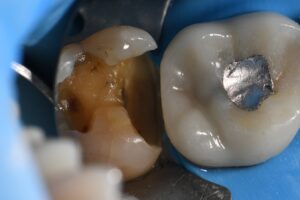

March 10, 2026 (Afternoon tea pics 2341.3: Kerr Simplishade | Rhondium DME | Garrison Dental Solutions – North America) Getting d o w n with DME. #RhondiumDME #KerrSimplishade #GarrisonCompositight Previous Post